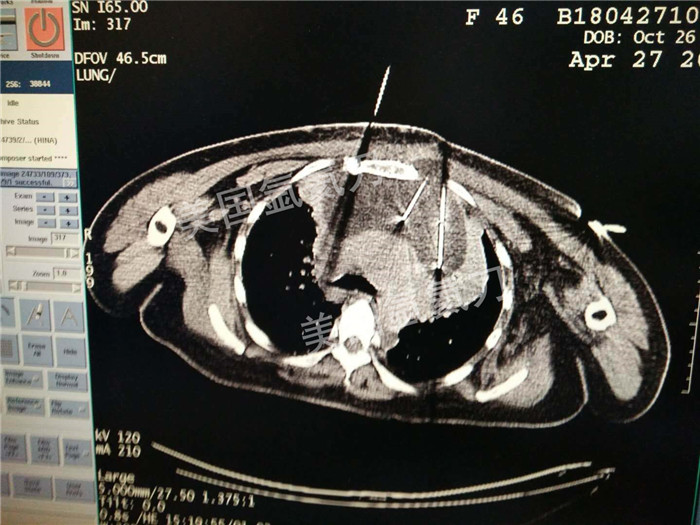

河北省中医院肿瘤科王利民主任胸腺19公分肿瘤氩氦刀手术

图片版权归美国氩氦刀所有,仅用于美国氩氦刀的宣传交流